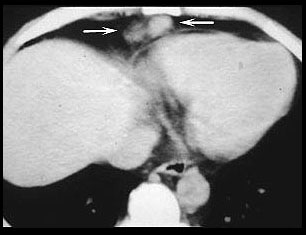

There is an enlarged right paracardiac lymph node (arrows). CT shows more lymph nodes than radiographs and more accurately locates the nodes. This is important in deciding which procedure should be used; mediastinoscopy, bronchoscopy, Chamberlin procedure, or percutaneous biopsy, if it is necessary to biopsy a node. |